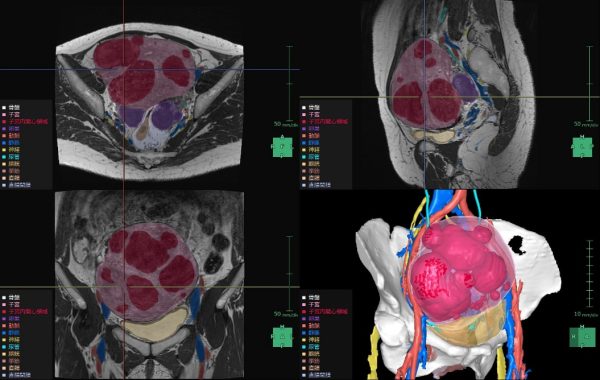

子宮筋腫は、成人女性の罹患率が20~30%と高頻度に見られる疾患で、機能温存が重要とされている。MRIや超音波画像診断装置の2D画像では筋腫や周囲組織の3次元的な把握が難しく、骨盤内の複雑な解剖構造の理解も困難である。また、筋腫の大きさや数、妊孕性温存の希望などにより様々な手技が適用されるが、筋腫の計測や手技の選択は各医師の経験則や感覚に基づいて行われているという課題がある。「婦人科臓器解析」ではMRIのT2画像からAI技術を活用した抽出エンジンを用いて子宮周囲の臓器をセグメンテーションし、ユーザーが子宮筋腫と判断した箇所の体積・数・深さの定量化を行うことができる。また、3Dで周辺組織との位置関係を把握することで筋腫手術の低侵襲化や取り残し防止等への寄与が期待される。

婦人科臓器解析の解析画面